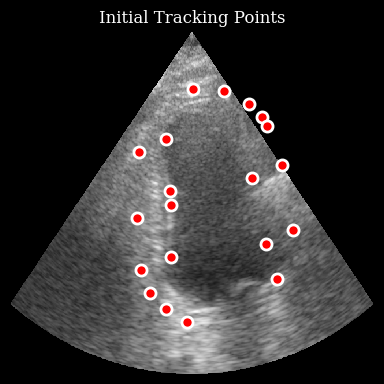

Track points

Initialize the tracker and track through the sequence:

[8]:

tracker = LucasKanadeTracker(win_size=(32, 32), max_level=3, max_iterations=max_iterations)

trajectories = tracker.track_sequence(frames, initial_points)

Now we can visualize the trajectories of the tracked points:

[9]:

viz_frames = []

for t in range(n_frames):

fig, ax = plt.subplots(figsize=(4, 4))

ax.imshow(frames[t], cmap="gray", aspect="auto")

for i in range(n_points):

traj = np.array(trajectories[i][: t + 1])

if len(traj) > 1:

ax.plot(traj[:, 1], traj[:, 0], "r-", alpha=0.4, linewidth=2)

ax.plot(

traj[-1, 1],

traj[-1, 0],

"o",

color="red",

markersize=8,

markeredgecolor="white",

markeredgewidth=2,

)

ax.set_title(f"Frame {t}/{n_frames - 1}")

ax.axis("off")

fig.tight_layout()

viz_frames.append(matplotlib_figure_to_numpy(fig))

plt.close(fig)

save_to_gif(viz_frames, "tracking_result.gif", fps=10)

zea: Successfully saved GIF to -> tracking_result.gif

Tracking Result